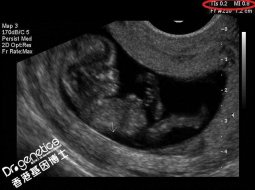

• B超单真的能鉴别男女吗? B超单真的能鉴别男女吗? 日期:2019-10-18 09:08:27 点击:52

孕妇在整个怀孕期间都要做b超检查。通常我们会带b超去看医生。我们可以自己看一些基本数据。那么这些数据真的与性别有关吗? B超单怎么看 胎儿性别的B超数据。 在一般情况下,...

• 彩超上的3个数据看男女,最准确鉴别男女的方法 彩超上的3个数据看男女,最准确鉴别男女的方法 日期:2019-10-17 09:21:24 点击:142

从怀孕开始,宝妈们就对宝宝的性别非常的关注,与重男轻女没有关系,就单纯的好奇,再加上国家已经全面开放二胎政策了,很多原本有想法的家庭纷纷开始行动起来,一心只想要给...

• B超数据透露胎儿性别? B超数据透露胎儿性别? 日期:2019-10-16 09:18:55 点击:25

利用超声等技术手段进行非医学需要的胎儿性别鉴定,以便人工终止妊娠,在我国,这一行为被明令禁止。但是受传统观念的影响,不少家长还是希望能提前得知胎儿的性别。不少准妈...

• 三维彩超怎么看男女准不准 三维彩超怎么看男女准不准 日期:2019-10-12 09:08:52 点击:82

三维b超怎么看男女准不准?如何从三维彩色多普勒超声数据看男女??许多想做母亲的人想做一个三维B超来评价婴儿的身体健康指数,许多母亲想要满足自己的好奇心,看看婴儿是男...

• 香港验血一定要有B超单证明吗? 香港验血一定要有B超单证明吗? 日期:2019-08-31 00:14:45 点击:42

经证明,在45天以上的妊娠和B超可被证实,因此必须记住在香港采取B超检查。如果不可能去香港进行B超检查,会很麻烦,建议内地的宝鸡做得很好,把它带到香港去。但是,我们在互...

• 香港验血和B超哪个才能知道男女? 香港验血和B超哪个才能知道男女? 日期:2019-08-10 09:40:42 点击:97

许多孕妇想根据B超的数据来判断男娃和女 娃 。双顶径(胎头横径)减去股骨长度(股骨大腿骨长度)的值大于2。它是一个男性宝藏,少于2个,和一个女性宝藏。简而言之,男孩的头...

• 怀孕期间孕妈妈牢记B超的3个检测时间段 怀孕期间孕妈妈牢记B超的3个检测时间段 日期:2019-07-21 09:19:43 点击:36

怀孕的母亲们知道怀孕期间超声波是不可或缺的。 超声波不仅能让怀孕的母亲们看到婴儿的样子,还能检测出婴儿的健康状态。 超声波虽然不怎么影响,但必须控制超声波的次数。 现...